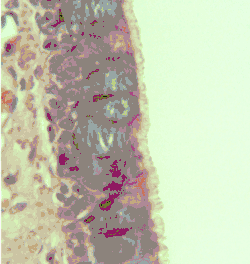

Additional images

- Cross-section of pseudostratified columnar epithelium

- Second cross-section